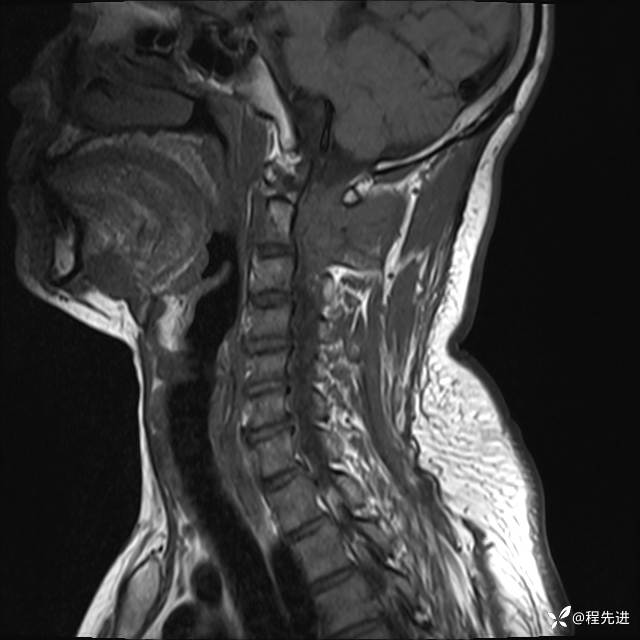

MRI平扫+增强:

T2:

T1: